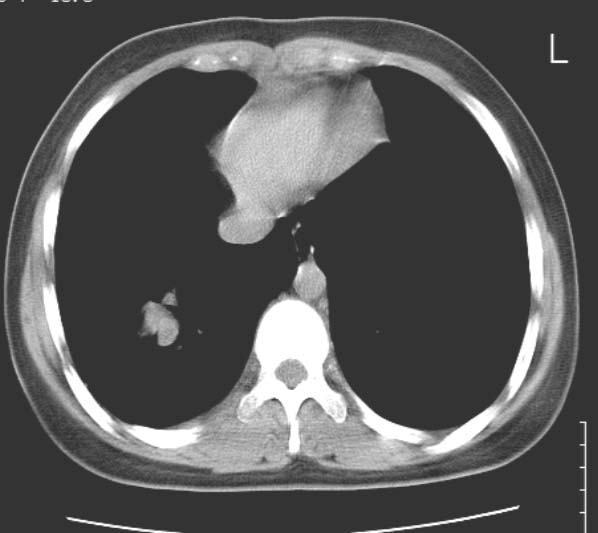

标题: CT25816:胸部CT,请会诊。

女 19岁,发热,咳嗽

考虑血管畸形。建议临床进一步检查。

考虑肺血管畸形可能性大,建议增强检查。或薄层ct后三维重建。

考虑右下肺动静脉畸形,建议增强进一步检查。

右下肺静脉畸形可能,建议增强

1、右下肺动静脉畸形?2、右下肺囊肿?建议ct增强扫描。

动静脉瘘可能,增强吧.

血管畸形可能性大

考虑右肺下叶支气管扩张并黏液嵌塞。